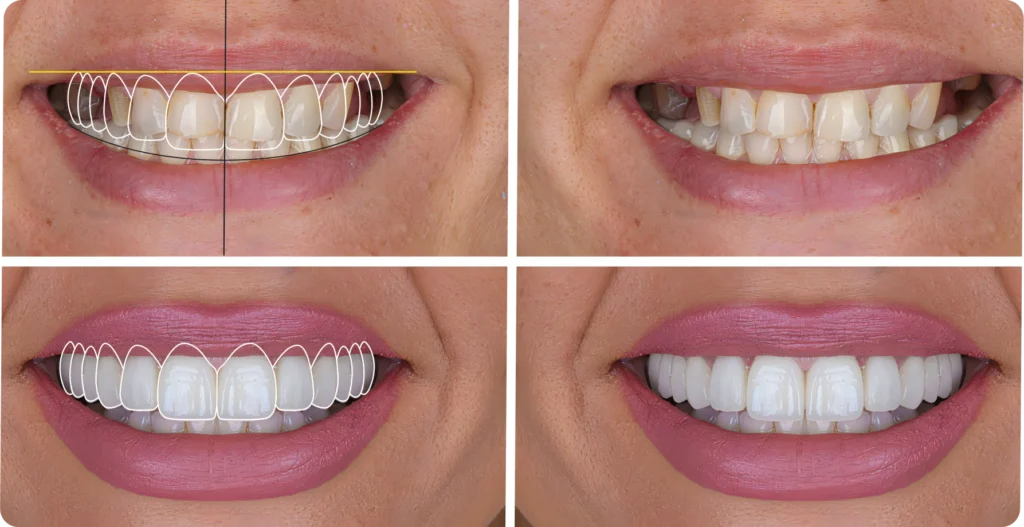

La planification esthétique au cœur du projet prothétique

La planification esthétique joue un rôle important dans la réhabilitation prothétique esthétique globale.

Elle permet d’analyser les proportions dentaires, la ligne du sourire, l’équilibre gingival et la relation entre les dents, les lèvres et le visage. Le projet ne repose donc pas uniquement sur l’état des dents. Il prend aussi en compte l’harmonie générale du sourire.

Cette étape facilite également la compréhension du traitement. Le patient perçoit mieux la logique du projet. De son côté, le praticien explique plus clairement ses choix. Par conséquent, le dialogue devient plus simple et plus constructif.

Le traitement suit généralement plusieurs étapes. D’abord, le praticien réalise un bilan clinique complet. Il observe l’état des dents, des gencives, de l’occlusion et du sourire. Cette première phase permet d’identifier les besoins fonctionnels et esthétiques.

Ensuite, le praticien mène une analyse plus précise du sourire. Il évalue les volumes, les proportions et l’équilibre général. Cette étape l’aide à définir les objectifs du traitement et à construire une stratégie cohérente.

Puis, il sélectionne les solutions prothétiques selon le cas. Dans certaines situations, des restaurations provisoires ou des maquettes d’essai peuvent aider à valider le projet avant la phase définitive. Ces outils permettent d’ajuster certains détails et de sécuriser le résultat final.

Enfin, le praticien pose les restaurations définitives selon le plan établi. Le traitement progresse ainsi de façon structurée, avec une attention constante portée à l’esthétique, à la fonction et au confort.